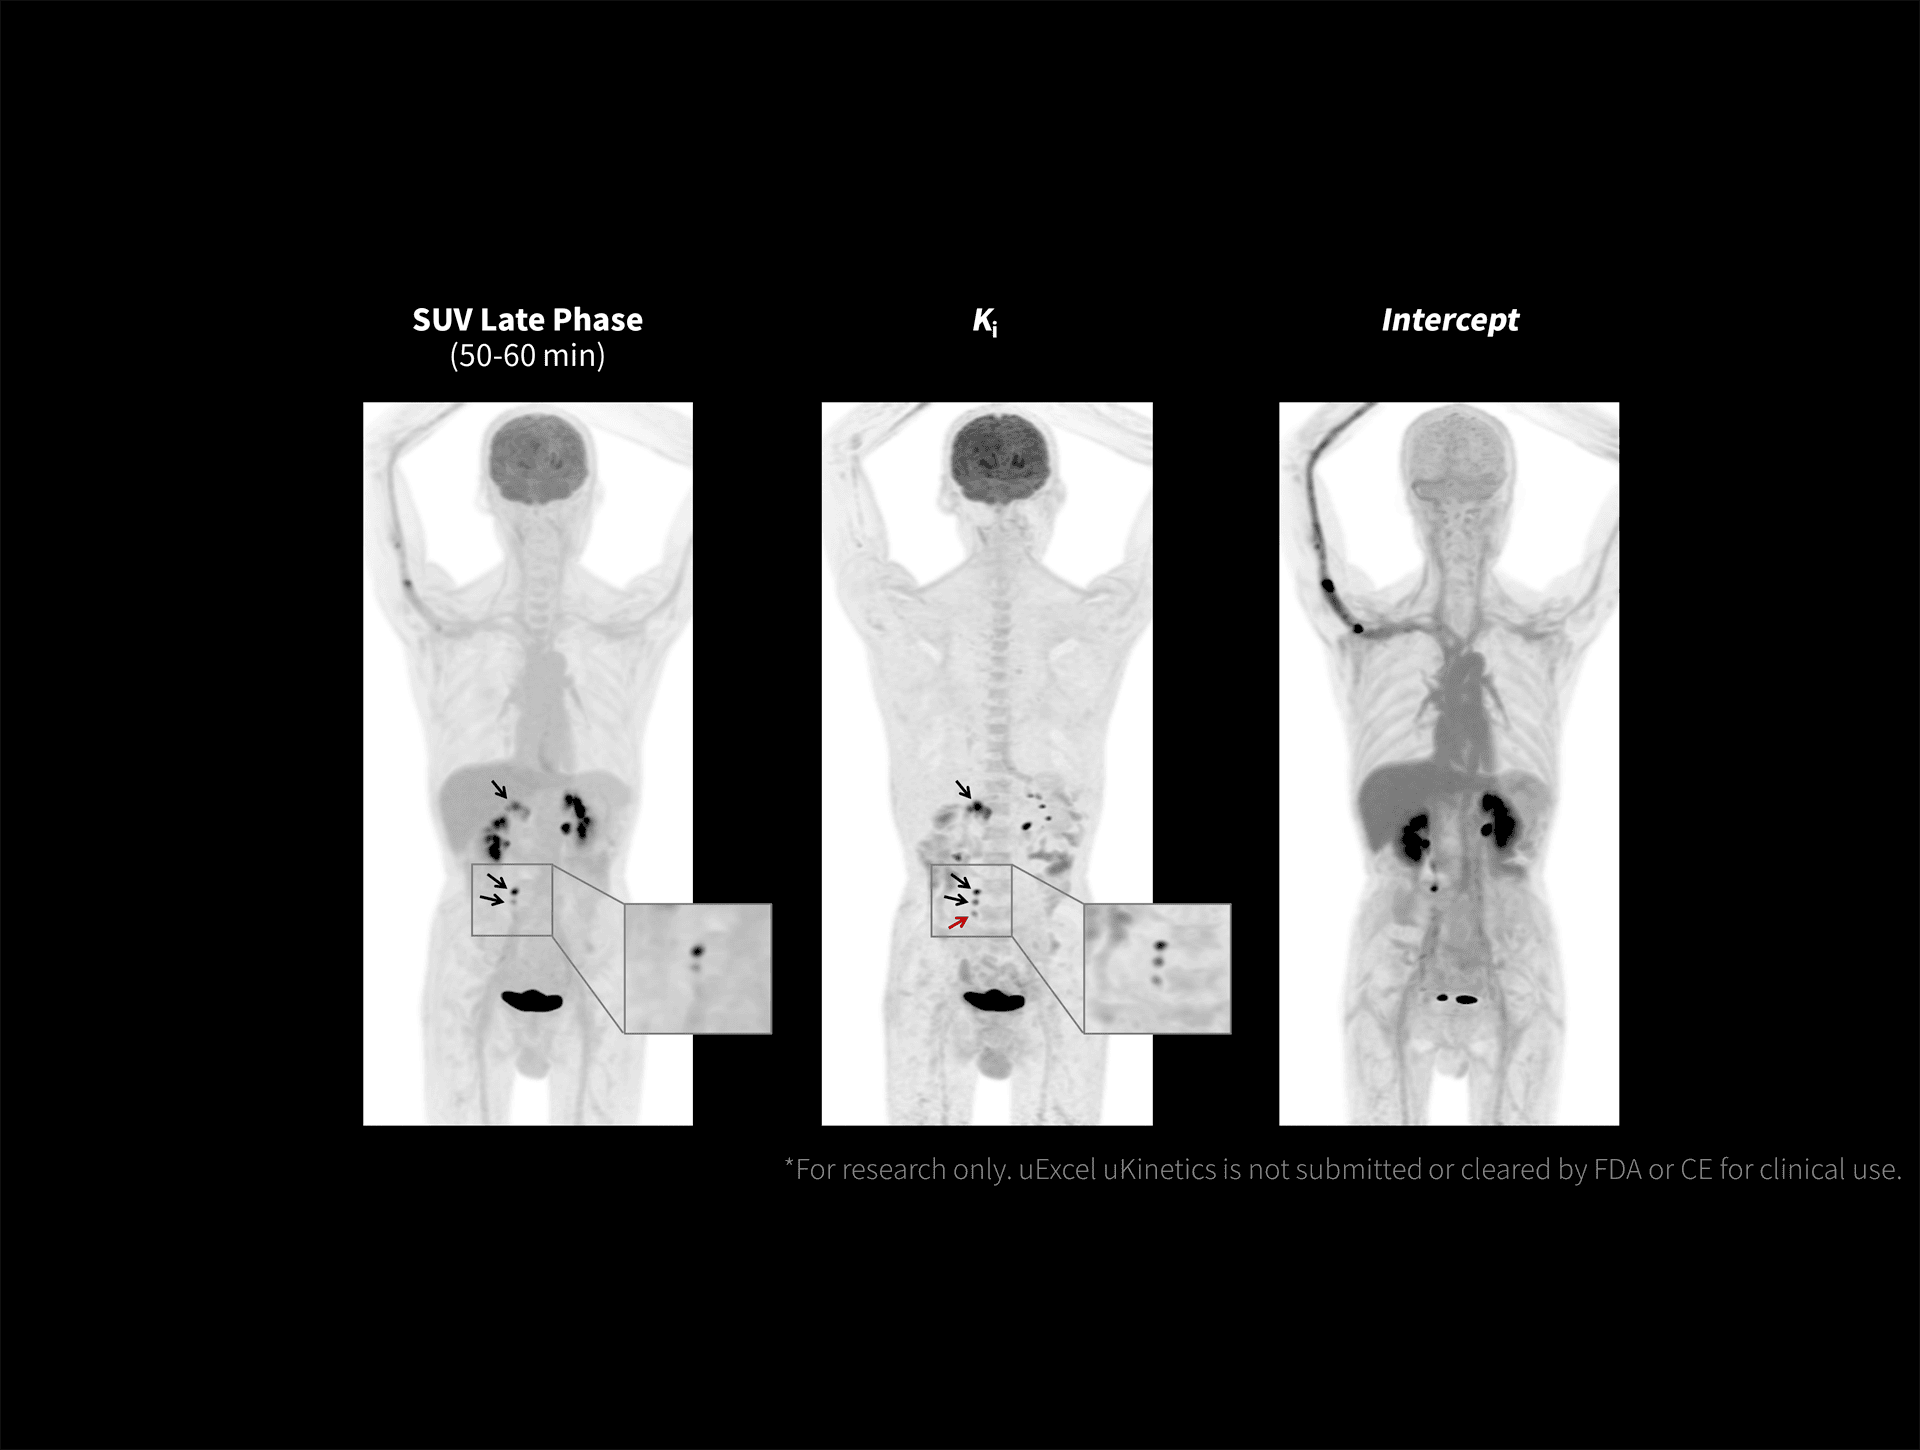

Imagistica KI evidențiază un contrast superior în cancerul pulmonar cu uKinetics